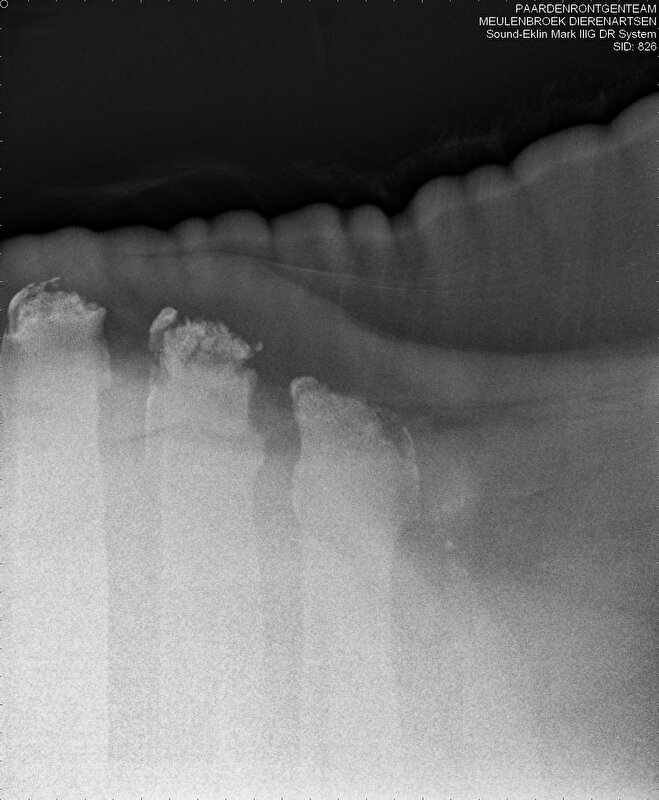

Deze twee röntgenfoto's zijn van de ruggengraat/schoft van mijn merrie. De dierenarts heeft me er een aantal dingen over kunnen vertellen, maar ik ben benieuwd wat kenners (of wellicht niet-kenners) hierover te zeggen hebben. Niet om mijn dierenarts te controleren hoor, maar meer om het plaatje voor mijzelf wat meer compleet te maken. Deze foto's geven het probleemgebied aan.

je ziet de brokkelstukjes al zitten is niet mooi afgerond vergeleken bij de andere wervels, je kunt het verschil goed zien

nou het lijkt me niet moeilijk om te zien dat daar iets helemaal fout zit, zeker in vergelijk met de 'gladdere' wervels ernaast. Is dat (verregaande) artrose?

Dit is het beeld dat je bij mensen met gevorderde reumatoide artritis ziet: bot-erosies.

RA komt echter niet voor bij paarden, dus dit is wel heel apart.

Je kunt heel duidelijk zien dat er wervels mooi glad zijn en de wervels meer naar voren kapot/afgebrokkeld zijn. Je ziet heel ligt nog wel de contour van de wervel, dus ik neem aan dat het iets van botafbraak is. Nu weet ik niet of dit zo plaatselijk voor kan komen, aangezien de andere wervels er nog wel netjes uit zien. Ik denk niet dat deze pony achterover is gevallen, in mijn ogen zou het dan nog veel meer versplinterd moeten zijn.

Ik vind trouwens ook dat de ribben (?) van de aangetaste wervels er minder glad en strak uit zien dan die van de onaangetaste wervels. Ook de eerste wervel links van de eerste aangetaste wervel die je al wat minder zwart wat volgens mij duidt op een kleinere dichtheid van het botweefsel.

Op foto 2 zie ik dat het paard met de hals gedragen staat, dus niet met hoofd naar beneden, klopt? Volgens mij verregaande artrose met boterosie. Je ziet zeker op die 2e foto heel mooi dat de botwoekering rechts op de zijkant van de wervel netjes lijkt de passen in de "holte" van de wervel daarnaast. Om die reden zou ik zelfs KS niet durven uitsluiten, ter hoogte van de schoft zeg maar. Mogelijks door foutieve houding of nadelige bouw van het paard in opgerichte houding. Al denk ik niet dat een ruiter hiervan de oorzaak kan zijn, dan zou je je paard bij wijze van spreken in een pers bij elkaar moeten gepropt hebben.

Bovenaan de wervels zie ik meer densiteit (meer wit) dan onderin. Is er sprake van verkalking of iets soortgelijks?

Op de onderste foto zie ik ook 2 wervelkoppen om het zo te zeggen en dan heel vaag uiterst rechts nog een 4e, maar die lijkt me zelfs bijna recht afgebroken te zijn of zoiets? Het ziet eruit alsof er een hele wazige mespunt zit ipv een halswervel.